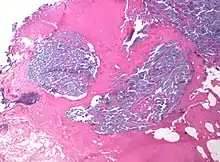

Desmoplastic small round cell tumour, with desmoplasia surrounding nests of cancer cells.

In medicine, desmoplasia is the growth of fibrous connective tissue.[1] It is also called a desmoplastic reaction to emphasize that it is secondary to an insult. Desmoplasia may occur around a neoplasm, causing dense fibrosis around the tumor,[1] or scar tissue (adhesions) within the abdomen after abdominal surgery.[1]

Desmoplasia is usually only associated with malignant neoplasms, which can evoke a fibrotic response invading healthy tissue. Invasive ductal carcinomas of the breast often have a stellate appearance caused by desmoplastic formations.